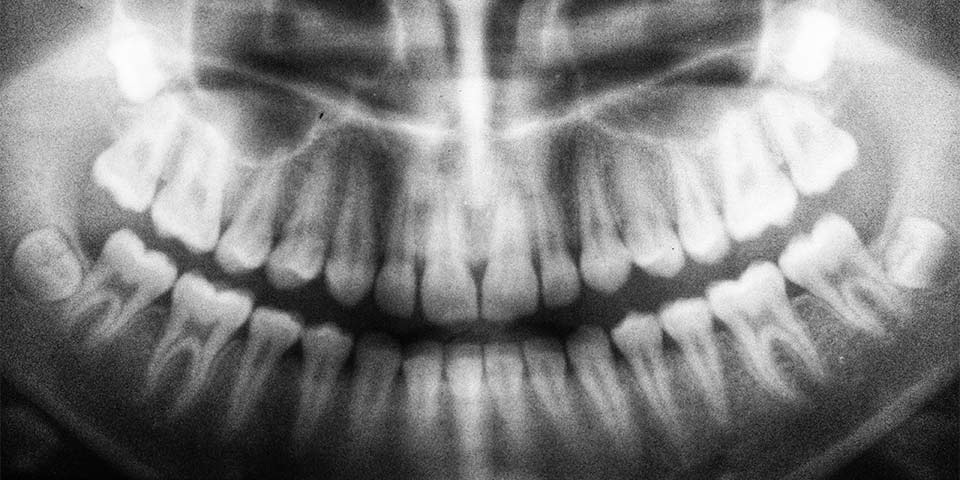

“Dijital panoramik röntgen ne demek?” sorusunun cevabına gelirsek diş doktorunuza ağız içerisindeki; diş, çene, damak, diş etleri kısımlarını en küçük ayrıntılarına kadar gösterebilen bir röntgen türüdür. Diş doktorları, dijital panoramik röntgen yorumlama konusunda kolaylık yaşamaktadırlar.

Yöntem kullanılarak ağız içerisindeki büyük sinirlerin, gelişen dişlerin, sinüslerin ve patolojilerin yerleri rahatlıkla tespit edebilir. Ayrıca çene eklemleri ve ağızdaki kemikler de kontrol içerisinde yer alır. Bu açıdan ağız için mükemmel bir genel tarama olduğu söylenebilir.

Dijital panoramik röntgen; alt ve üst çeneler, tüm dişler, burun bölgesi ve sinüslerine ek olarak temporomandibular eklemleri tek bir görüntüde toplar. Söz konusu görüntü, kavisli çene yapısının tersine düz bir görüntüdür. Böylece diş hekimi görüntü üzerindeki değerlendirmeleri hem daha kolay gerçekleştirir hem de daha doğru tespitler ortaya koyar.

Panoramik röntgen, ağız içi ve çevresinde, çene, diş ve bütün bölgelerin en ince ayrıntılarının tek bir görüntü üzerinde toplanmasıdır. Panoramik röntgen sayesinde ağız ve diş hastalıkları konusunda erken teşhis ve tedavi mümkün hale getirir.